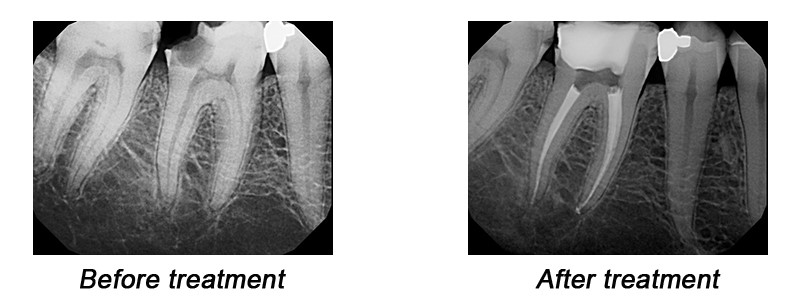

Root Canal Treatment (RCT) is the removal of the tooth's pulp, a small, thread-like tissue in the centre of the tooth. Once the damaged, diseased or dead pulp is removed, the remaining space is cleaned, shaped and filled. This procedure seals off the root canal. Years ago, teeth with diseased or injured pulps were removed. Today, root canal treatment saves many teeth that would otherwise be lost.

To determine the success or failure of root canal treatment, the most relied-upon method is to compare new X-rays with those taken prior to treatment. This comparison will show whether bone continues to be lost or is being regenerated.